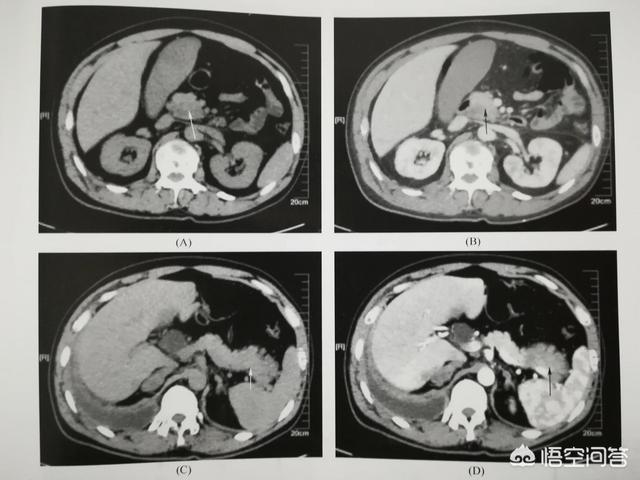

(如图为胰腺钩突部癌。63岁。患者两年前突发血糖升高。一直以为正常糖尿病。去年底被诊断为胰腺癌)

因此。对于50以上的人群。若新近发现糖尿病。应引起大家足够重视。有可能是胰腺癌的异常症状。属于患胰腺癌的高危人群。